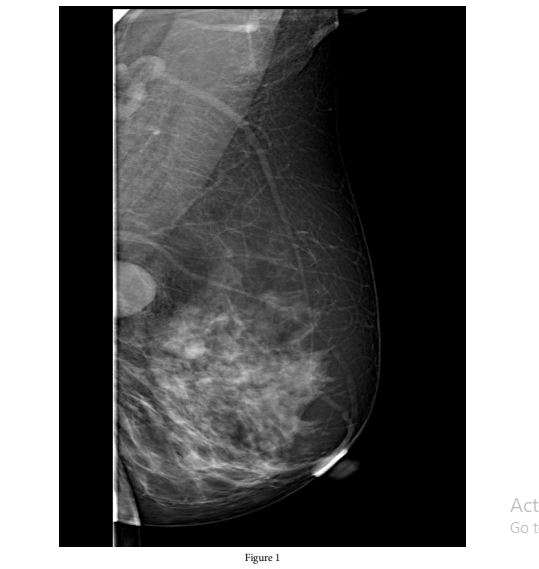

A 39-year-old female patient who did not have any medical history or von Recklinghausen’s disease presented to our center with complaints of pain and palpable hardness in the left breast for the past six months. On physical examination, there was a palpable mass in the upper outer quadrant of the left breast. Ultrasound revealed a well-circumscribed, oval lesion containing cystic areas, measuring 15x22x26 mm in the upper inner quadrant of the left breast. Vascular structures were observed within the slightly cellular fibrolipomatous stroma in serial sections of the core biopsy. According to the mammography performed one year later, there was a 13x28-mm, well-circumscribed, oval opacity on left mediolateral radiography (Breast Imaging-Reporting and Data System [BI-RADS] category 4a findings) (Figure 1).

The clinical and radiological appearances of schwannomas are similar to those of benign tumors [8]. On ultrasonography, schwannomas are defined as solid and hypoechoic masses with variable degrees of posterior acoustic shadowing [9]. However, our patient’s ultrasound revealed a well-circumscribed, oval lesion containing cystic areas. The patient was followed up with a diagnosis of cystic disease in the breast. The mammographic findings of these tumors are usually defined as non-specific, appearing as round or oval densities, although some normal mammographic findings have also been described [8]. In our patient’s mammography, a well-circumscribed, oval opacity was observed.